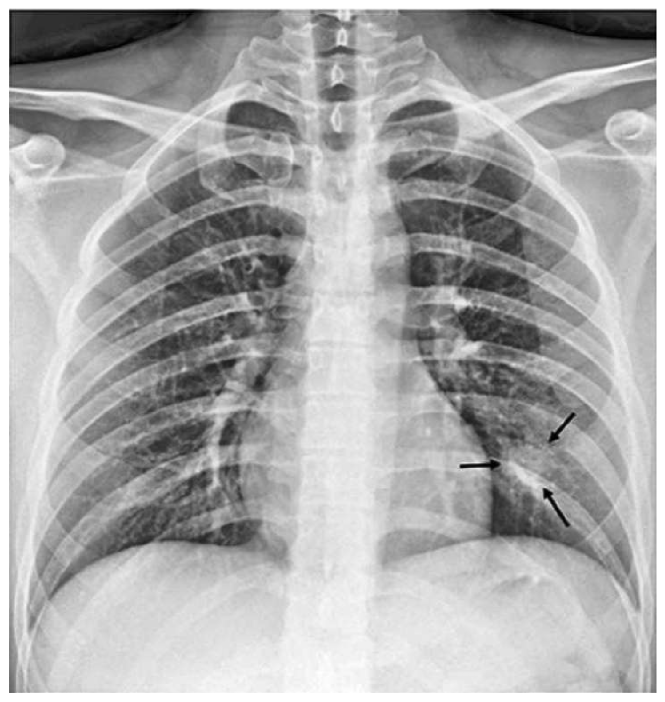

Regarding CheXNet pretrained model, we first probe to see if it is capable of correctly classifying COVID-19 pneumonia with no further improvements. Fig. 14 shows results for two sample CXRs from both classes.

Refer to caption

(a)

(b)

Figure 14: CheXNet probabilities of different classes for (a) a COVID-19 positive case, and (b) a normal case

Extracted heatmaps reveal that CheXNet correctly marks chest lobes to determine each class probability. The output of each class is slightly higher in positive cases for most of the diseases as well. Some of the drawbacks are extremely high predictions for infiltration in most of the dataset images, getting stuck in regions outside lung boundaries and predominantly in corners, and missing some of the opacities particularly in lower lobes.